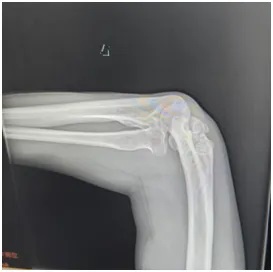

刘师傅赶忙来到郑州大学第五附属医院骨科一病区就诊。接诊医生为他安排了肘关节X线和上肢肌电图检查:

X线显示:肘关节存在明显畸形改变;

肘关节外翻角度从术前的30°左右,成功矫正到10°左右;

X线复查显示:钢板固定位置十分合适,骨头对位良好;